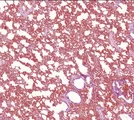

![]() | pylica płuc | 50%